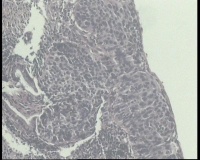

请老师 看看,宫颈活检,宫颈CINIII累腺局灶早期浸润还是直接报宫颈鳞癌?

鳞状上皮全层异型增生,局灶基底膜不清,请老师看看巢状分布的是累腺还是浸润?

CIN3累腺,不排除有浸润的可能。

有浸润,鳞癌